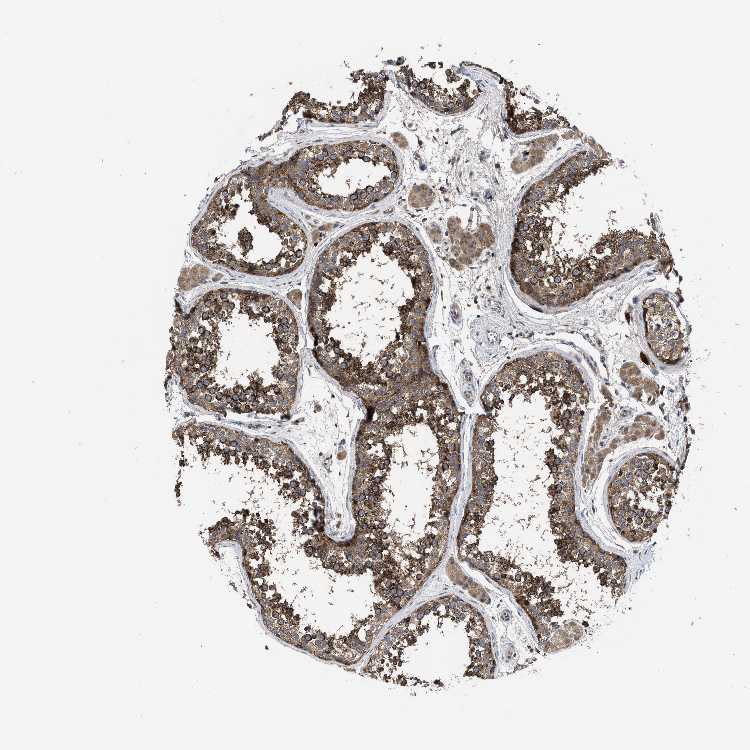

TESTIS - Antibody stainingi

Antibody staining in the annotated cell types in the current human tissue is reported as not detected, low, medium, or high, based on conventional immunohistochemistry profiling in selected tissues. This score is based on the combination of the staining intensity and fraction of stained cells.

Each image is clickable and will lead to virtual microscopy that enables deeper exploration of all samples and also displays staining intensity scores, fraction scores and subcellular localization as well as patient and tissue information for each sample.

Antibody HPA018162

Leydig cells Low

Elongated or late spermatids Medium

Pachytene spermatocytes High

Peritubular cells Not detected

Preleptotene spermatocytes Medium

Round or early spermatids High

Sertoli cells Medium

Spermatogonia cells High